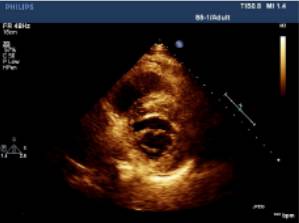

左边为法洛氏四联症的患者,肺动脉发育不良,肺动脉有14mm明显变窄;右侧是肺动脉高压的患者,肺动脉明显增宽,为32mm。